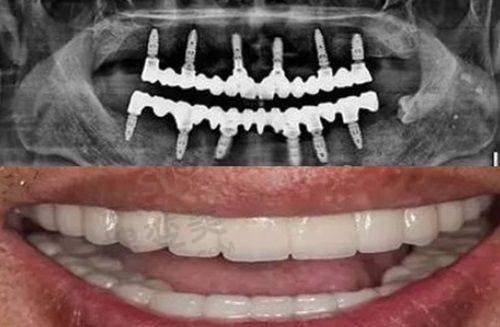

作为12家连锁分院之一,合肥中诺共享集团技术——立得用即刻种植系统。这个系统可实现“当天种牙、当天戴牙”,尤其适合骨缺损患者免植骨修复,半口种植仅需4 - 8颗植体。该技术已累计完成超3000例复杂病例,成功几率在95%以上。医院的硬件配置也十分精良,5000㎡独立院区,配备德国卡瓦CBCT(骨量分析精度0.1mm)、瑞士士卓曼种植机、3D数字化导板(误差

它是经卫健委审批后成立的正规二级口腔医院,还是国内外连锁品牌,有着二级专科资质,让患者看病更安心。医院的技术实力特别强,立得用种植牙技术是其特色之一,可以当天拔牙、当天种植、当天使用。比如李大爷,之前牙齿掉了好几颗,吃饭都成问题,在天津中诺口腔医院用立得用种植牙技术种了牙,当天就能吃东西。医院还引进了新型的口腔诊疗设备和技术,像3D口扫、CBCT牙片等。3D口扫能快速精细地获取口腔数据,医生根据这些数据制定的治疗方案更科学、更精细。

医院营业面积达4000平方米,是邯郸地区规模较大的私立口腔机构之一。院内设数字化种植中 心、正畸中 心、美学修复科等五大核心科室,并配备层流手术室与进口高端设备,如芬兰小牙片机、意大利Newtom CBCT机等,硬件条件达到精良水平。在特色技术方面,“立得用”种植体系在邯郸分院得到全方面应用。该技术通过3D数字化导板定位,实现微创种植、即刻负重,单颗种植仅需3 - 5分钟,半口或全口缺牙患者可当天完成种牙并修复咀嚼功能。医院还引进了精良的数字化美学矫正技术,结合DSD数字微笑设计,提升治疗精细度与美观度,无论是儿童还是成人,都能在这里找到适合自己的矫正方案。